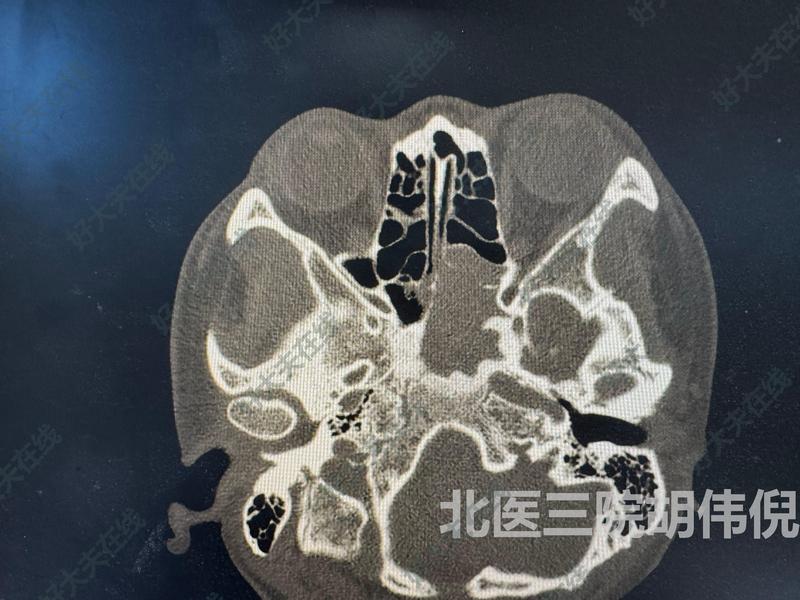

治療前患者34歲女性,主因間斷頭疼3周,加重2周入院。完善CT及核磁,考慮左側(cè)真菌性蝶竇炎可能性大。治療中入院完善術(shù)前檢查,行左側(cè)篩竇及蝶竇開放,鼻竇病變切除術(shù)治療后治療后3月術(shù)后3個月,患者頭疼癥狀消失,復(fù)查CT提示蝶竇病變被徹底清除,蝶竇口開放良好

胡偉倪醫(yī)生的科普號2025年01月12日210